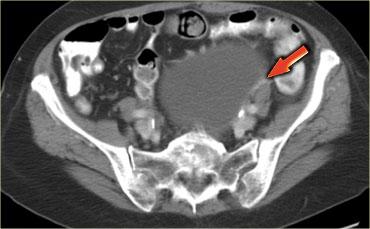

Trường hợp tiếp theo là siêu âm qua thành bụng cho thấy một khối nang đa thùy bên trái.

Hình ảnh này gợi ý u nang tân sinh buồng trứng nhưng không xác định được buồng trứng.

CT trên cùng bệnh nhân cho thấy một khối nang đa thùy tiếp giáp bàng quang, có liên quan đến tĩnh mạch buồng trứng trái (mũi tên).

Có các vách ngăn dày và thành dày không đều.

Dựa trên hình ảnh CT này, không thể phân biệt giữa tổn thương buồng trứng lành tính như u nang tuyến xơ và tổn thương buồng trứng ác tính.

Tổn thương được phẫu thuật cắt bỏ và kết quả giải phẫu bệnh xác định là u nang tuyến xơ.